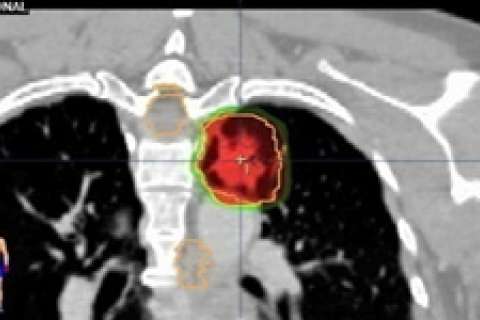

External beam radiation therapy targets your lung cancer. Radiation is given in a series of daily treatments, Monday through Friday. Treatments are painless and last less than 30 minutes.

- Conventional radiation therapy uses multiple radiation fields to target the cancer and keep radiation from healthy cells.

- 3-dimensional conformal radiotherapy (3D-CRT) combines multiple radiation treatment fields to deliver precise doses of radiation to the lung tumor. Tailoring each of the radiation beams to focus on the tumor targets the cancer while protecting nearby healthy tissue.

- Intensity modulated radiation therapy (IMRT) is a form of 3D-CRT that modifies the radiation by varying the intensity of each radiation beam. IMRT is still being studied for lung cancer.

- Stereotactic body radiation therapy (SBRT) is a specialized form of 3D-CRT that delivers high doses of radiation over a period of five to eight days. It is currently being evaluated for the treatment of lung cancer. This type of treatment is available at only a few centers around the country.

For early stage lung cancer, a highly focused and powerful form of radiation therapy called stereotactic body radiation therapy (SBRT) offers patients greater than 90% chance of success (local control) using a limited number of treatments (usually 3-5 treatments). For more advanced disease, a combination of radiation therapy, chemotherapy, and surgery is utilized to optimize the chance of cure. At UCLA, we offer state of the art technologies to treat early stage lung cancer with SBRT, as well as clinical protocols to increase the intensity of radiation therapy and shorten the treatment course for more advanced lung cancers.

The UCLA Department of Radiation Oncology utilizes a state-of-the-art Positron Emission Tomography CT scanner (PET/CT) for the planning of your radiation therapy when it is appropriate. We are one of the few radiation oncology departments in the country that has a dedicated PET/CT scanner used solely for the purpose of planning radiation treatments.